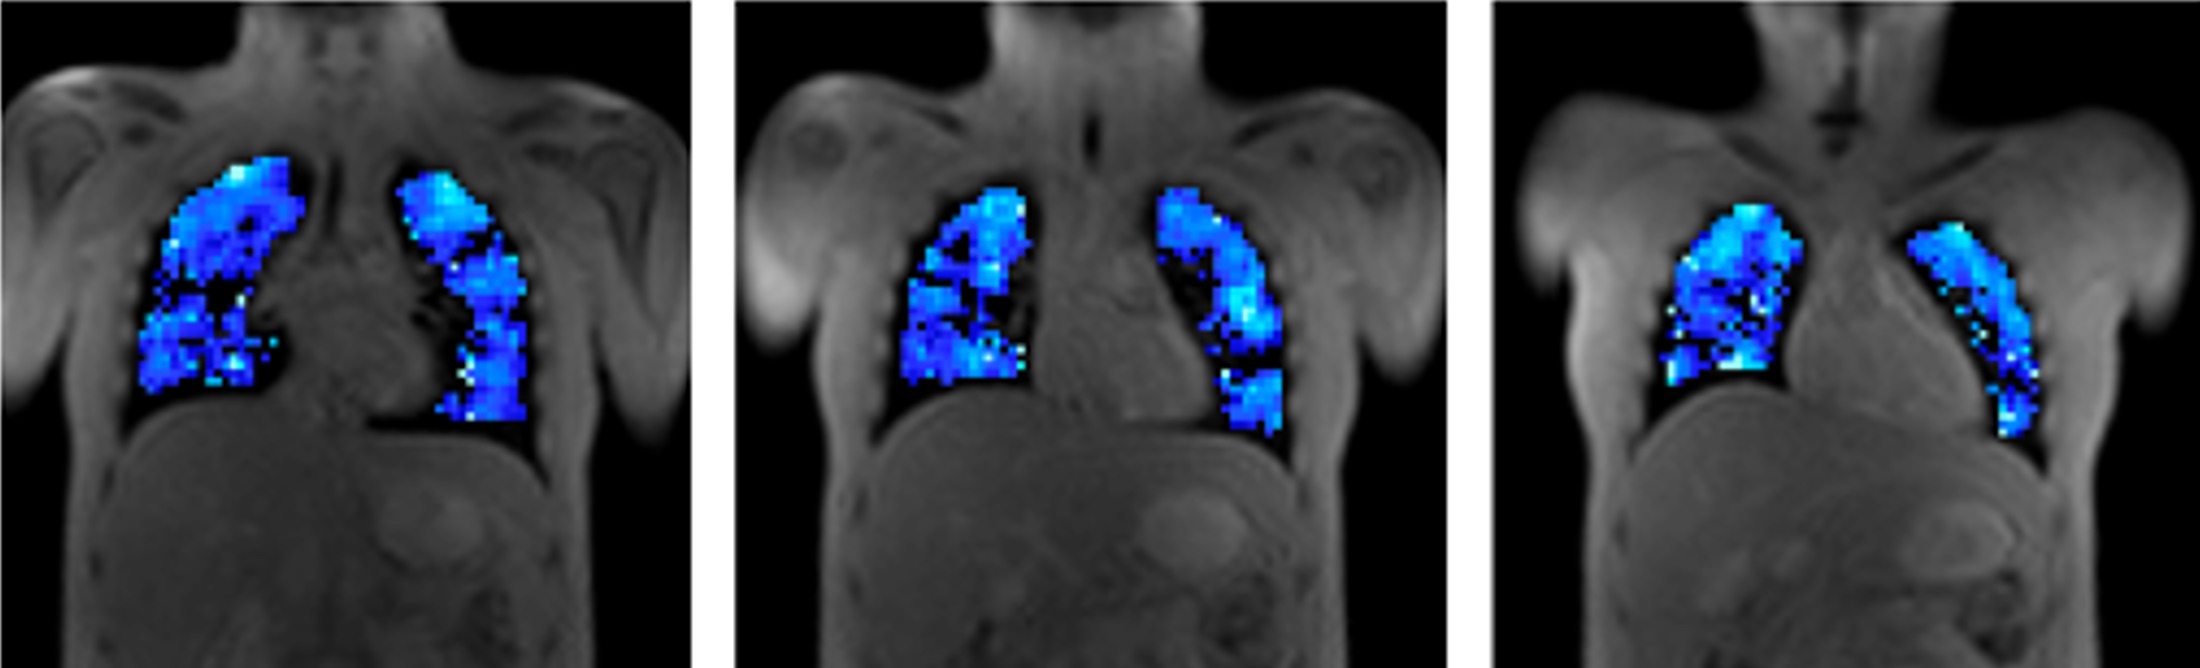

From study design to final reporting, Bioxydyn delivers repeatable MRI biomarkers that reveal tissue function, physiology and change. Our operational excellence and metrology help you compare results across sites, scanners and timepoints.

We're Bioxydyn - delivering quantitative MR biomarkers for pharmaceutical, biotech and academic studies. We combine scientifically leading methods with robust multi-centre study management and transparent analysis, turning complex images into repeatable measurements that support confident decisions.

Disease areas and services supporting quantitative MRI biomarkers across clinical trials.